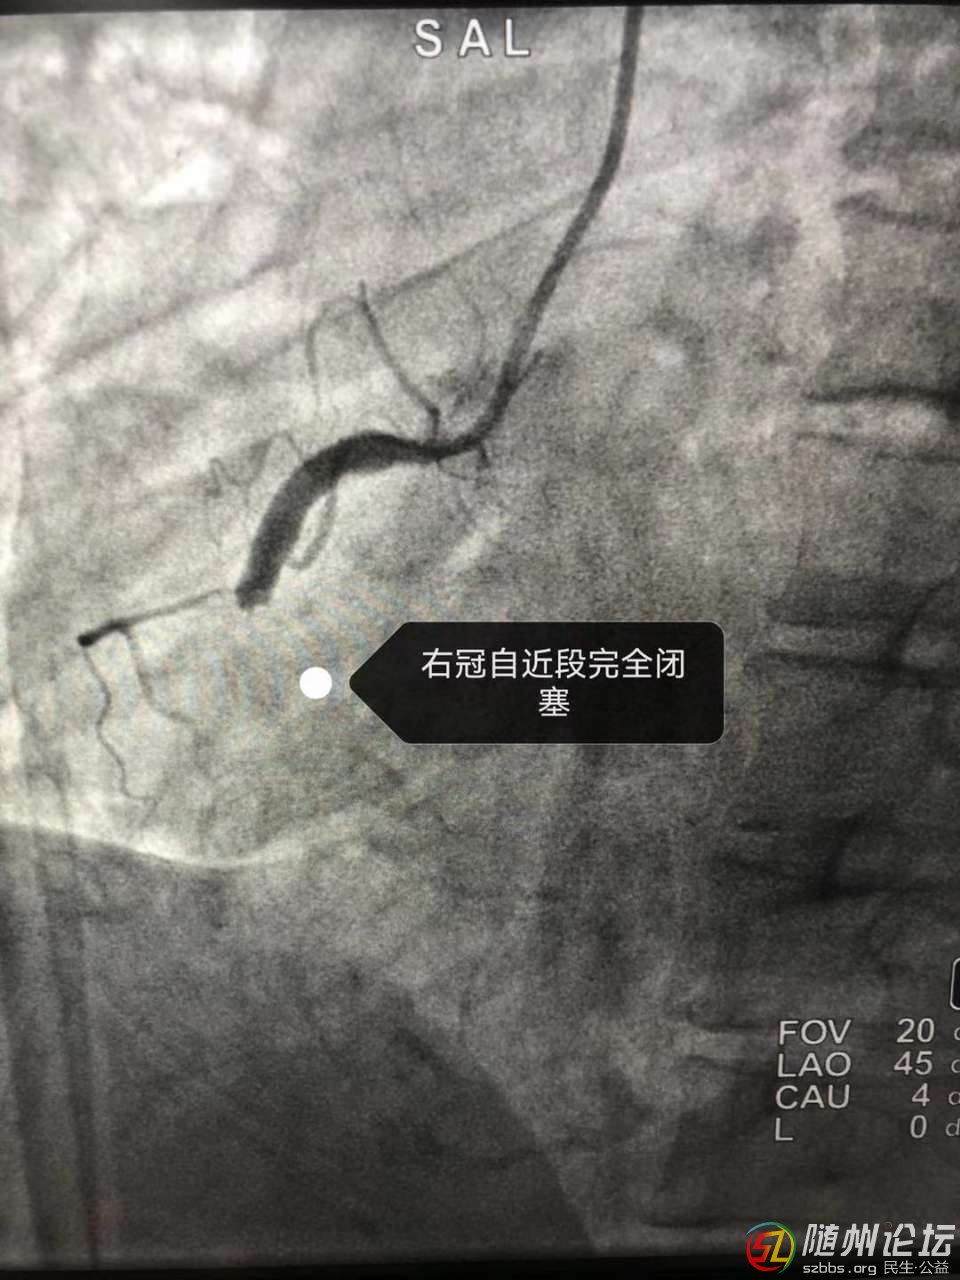

生死時(shí)速,再創(chuàng)生命奇跡——隨縣中醫(yī)醫(yī)院成功救治急性心梗并發(fā)室顫患者

近日,隨縣中醫(yī)醫(yī)院上演了一場(chǎng)“生死時(shí)速”,成功救治1例急性心肌梗死患者,患者黃女士,46歲,在上班途中突發(fā)胸痛、胸悶、失語(yǔ)、持續(xù)不緩解,周圍人員撥打120后急診科出診 ...